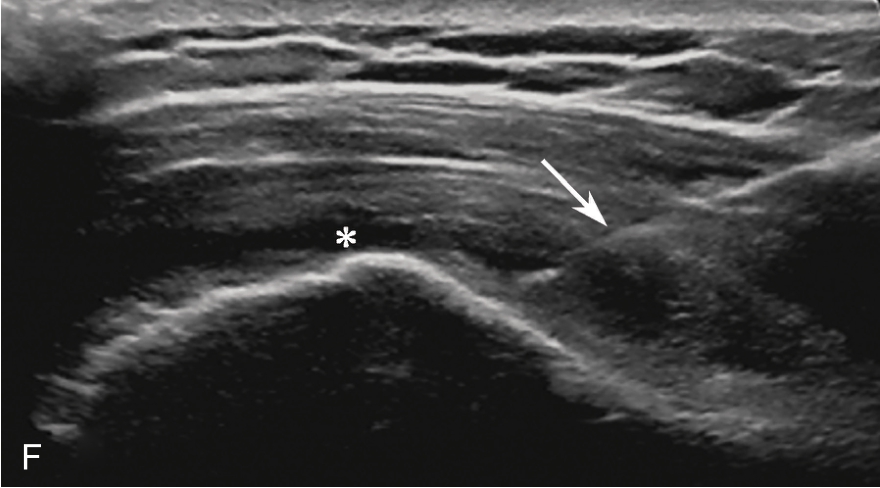

2.当针尖进入滑囊后(图2-1-5),可推注少量药物,若推注顺利可观察到滑囊扩张及药物的弥散(图2-1-6),同时也表明针尖准确位于滑囊内,可继续推注混合药物3~5ml。若推注受阻,原因有可能是针尖在滑囊组织内,需重新调整针尖,也可能是滑囊内粘连明显所致,可加大力度,利用液体推注的压力松解粘连,松解后可见粘连带呈线状稍强回声(图2-1-7),也可在粘连远端重新选择部位注入药物,这类患者可能需要多次治疗才能达到较好的疗效。

▲ 图2-1-5 超声引导下肩峰下-三角肌下滑囊穿刺治疗超声图

箭头:显示穿刺针尖进入滑囊;星号:冈上肌腱;H:肱骨头